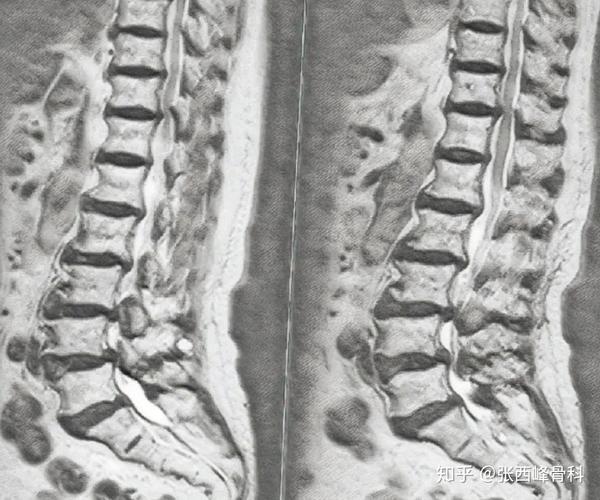

椎管狭窄影像学图片,椎管狭窄的片子图片

影像学显示:多间隙椎管狭窄

如何判断椎管狭窄超详细影像评估

椎管狭窄的片子图片

腰椎椎管狭窄图片

椎管狭窄图片

椎管狭窄图片解析

腰椎管狭窄图片讲解

怎么看腰椎管狭窄图片

什么是腰椎管狭窄图片